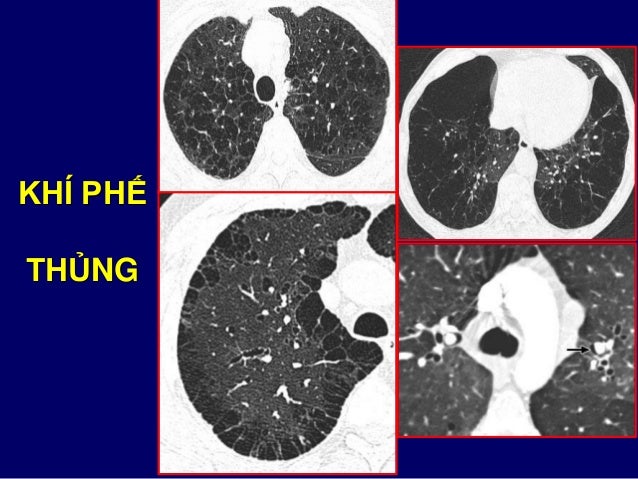

47. 47. KHÍ PHẾ THỦNG

48. 48. KHÍ PHẾ THỦNG THÙY TRÊN

49. 49. KHÍ PHẾ THỦNG THÙY DƯỚI

41. 41. BỌT / BÓNG KHÍ  Bóng khí: o Hình tròn giảm đậm độ, đ/k > 1 cm, thành < 1mm o Kèm khí phế thủng trung tâm tiểu thùy / cạnh vách  Bọt khí: o Hình tròn giảm đậm độ đ/k < 1 cm, thành < 1 mm o Hay nằm sát màng phổi o Ít ý nghĩa lâm sàng khi phân biệt bọt với bóng khí